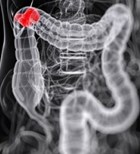

גילוי מוקדם של סרטן המעי הגס עשוי להציל חיים - ובדיקת הסקר...